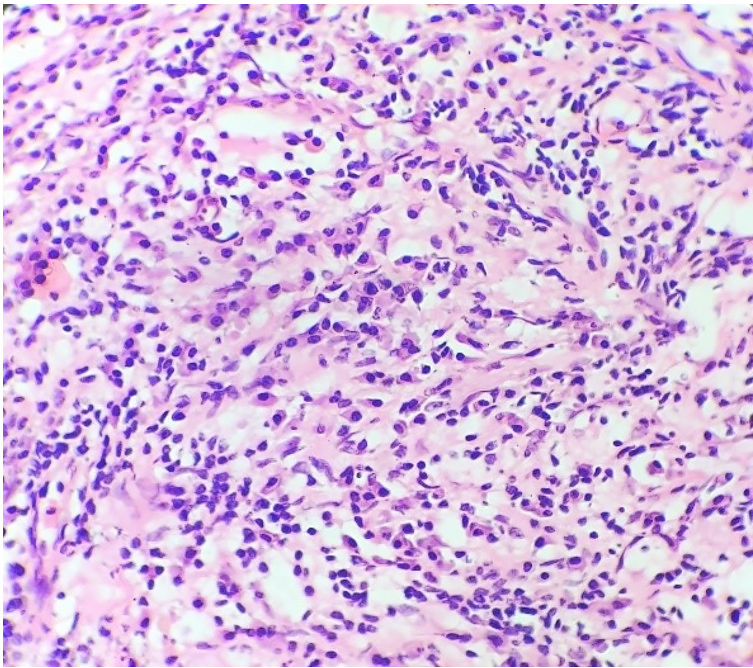

The patient then underwent elective surgery, and the surgical specimen of the excised space-occupying lesion was analyzed. The external surface of the specimen was smooth and firm. The cut surface was homogenous and yellowish-white in appearance. No areas of hemorrhage or necrosis were identified on the gross examination. The sample was fixed in 10% formalin, embedded in paraffin, and stained with Hematoxylin &Eosin (H&E), Periodic Acid Schiff (PAS), Gram and Ziehl-Neelsen (ZN) Stains. Microscopic findings revealed a lesion composed of fibro-collagenous stroma with interspersed endothelium lined blood vessels. Dense aggregates of inflammatory cells comprising predominantly of plasma cells along with lymphocytes were noted in the perivascular areas within the stroma (Figure 2).

Interspersed histiocytes with round vesicular nuclei and foamy cytoplasm were also noted. Normal brain parenchyma was noted at the periphery.

No meningothelial cells or psammoma bodies were seen. No atypia, mitosis, or necrosis was noted. PAS and ZN stains were negative for microorganisms. Histomorphological features favored the diagnosis of Intracranial Inflammatory Myofibroblastic Tumor. Immunohistochemical tests were done to confirm the diagnosis and to rule out monoclonal plasma cell proliferation. Immunohistochemistry was performed on deparaffinized sections of each case with CD138 (Dako), Vimentin (Dako), SMA(Dako), S-100 (Dako), CD68(Dako), Anti Kappa (Biogenex), Anti Lambda polyclonal sera (Biogenex) using avidin biotin peroxidase complex. Plasma cells were positive for CD138 and showed equal presence of kappa and lambda positivity. No evidence of clonal plasma cells was noted. Vimentin was diffusely positive in the stroma, SMA was positive in blood vessels. Histiocytes were positive for S100 and CD68. The diagnosis was confirmed as Intracranial Inflammatory Myofibroblastic Tumor. Additional serological tests were done to rule out Epstein Barr Virus (EBV) as infective etiology. EBV IgM ELISA was <10U/ML (<20U/ML: negative). EBV IgM to Nuclear Antigen was 2.64u/ml (<8: negative). EBV IgG ELISA was 0.42(<1.00 Negative). This case prompted us to review the literature on cases of Intracranial Inflammatory myofibroblastic tumor.